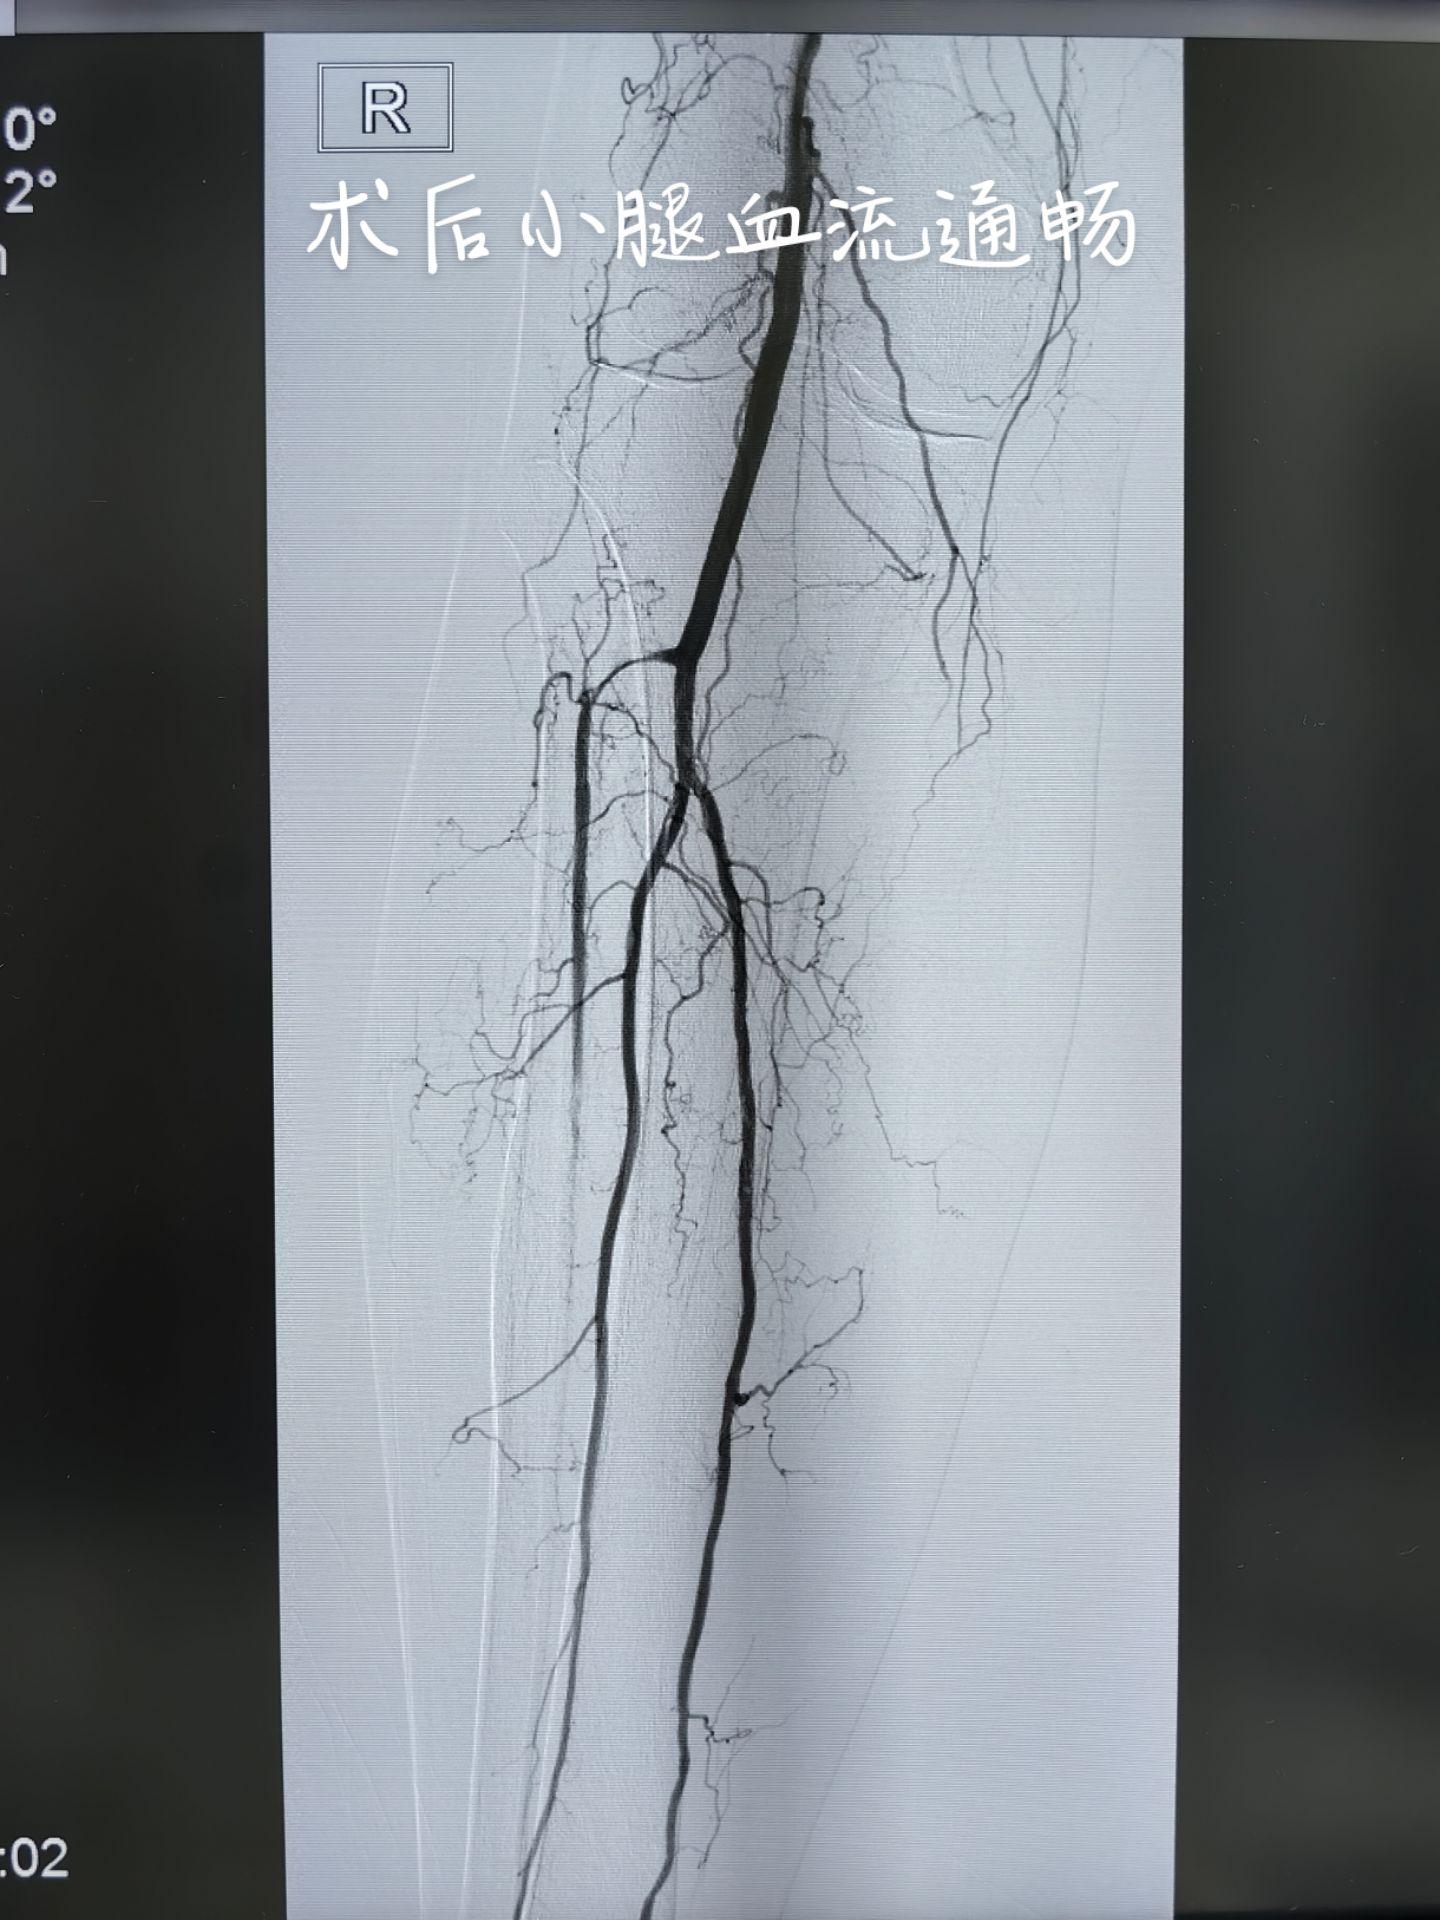

房颤心房血栓脱落引起下肢动脉栓塞,下肢冰冷、发绀,不及时处理会导致下肢坏死截肢,当地没有治疗条件,通过网络医疗联系到我,今天加台开通血管,冰冷发绀的下肢转为温暖红润,保肢成功[胜利